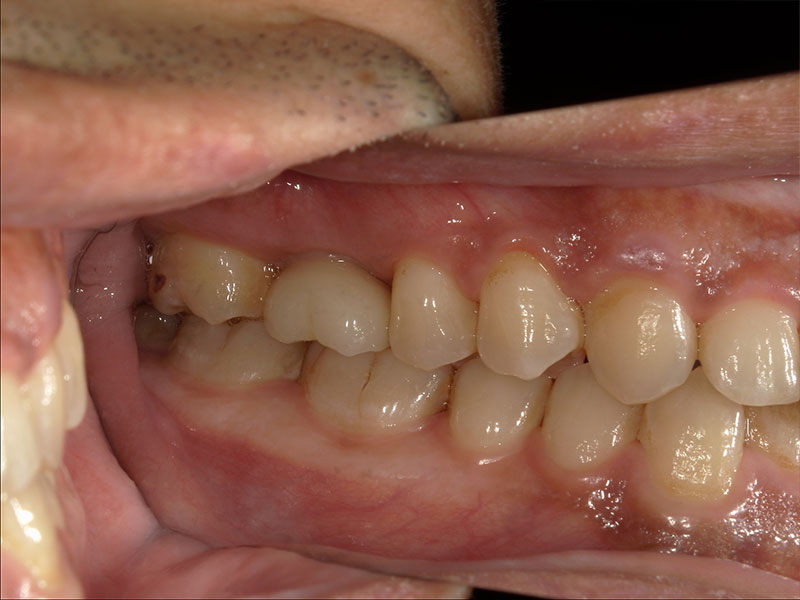

患者様は66歳、女性の方で、主訴としては右下の奥歯の治療をしたいとのことで来院されました。元々の当院に来院されたきっかけとしては、元々他院に行かれていたのですが、左右両側の親知らずの周囲の歯茎が炎症を起こし痛みを繰り返していたのですが、過去に顎が外れたことがあるらしく、そこから怖くて大きくお口を開けれないとのことでした。お口が開きにくいことから抜歯が困難とのことで他院ドクターからそのまま患部の洗浄をしながらの様子見でずっと過ごされていたとのことです。そこで当院に来院していただいてお口を見させていただいたのですが、意外とお口を開けていただくことができたので、親知らずの根っこの形態や生え方など総合的に考慮して、器具さえ入れば抜歯できると考え当院で抜歯させていただきました。抜歯の際は顎が外れないように患者様自身の手で少し押さえてもらいながら行いました。初めはとても不安そうだったのですが、案外すんなりと抜歯できたのでよかったです。そこから安心していただいたのか残りの反対の方の親知らずも抜歯しました。そして最終的には右下のインプラント治療を任せてもらうことになりました。

右下6の状態としては虫歯が進行していて、保存不可の状態でした。患者様との相談の結果、インプラント治療を行うことになりました。